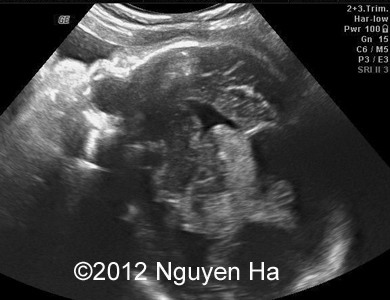

A 30-year-old woman (G1P0), with unremarkable family history, presented to our unit at 36 weeks of her pregnancy. She did not undergo any previous screening tests. Our examination (and repeated scan after four days) revealed following findings:

Figures 1-7: 36 wekks of pregnancy.

A 30-year-old woman (G1P0), with unremarkable family history, presented to our unit at 36 weeks of her pregnancy. She did not undergo any previous screening tests. Our examination revealed unilateral hypoechoic inhomogeneous mass within cerebral parenchyma. Our initial diagnosis was teratoma, but repeated exam after four days showed structural changes and different echogenicity of the mass and so our final diagnosis was cerebral hemorrhage. The findings were confirmed by MRI scan.

Figure 1-7: 36 wekks of pregnancy.